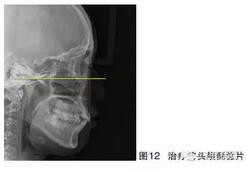

患者女,24歲,主訴“牙齒不齊”?;颊呙嫦窦翱趦?nèi)像如圖10~11所示,頭顱側(cè)位片如圖12所示。臨床檢查可見:上下頜中度擁擠,上頜尖牙頰向遠(yuǎn)中錯位,磨牙關(guān)系Ⅰ類尖窩關(guān)系,前牙輕度唇傾,口外觀、換成嘴唇輕微前突。診斷:牙列擁擠伴輕度齒槽性前突。